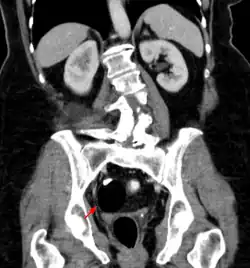

| A small (4 cm) dermoid cyst of an ovary, discovered during cesarean section | |